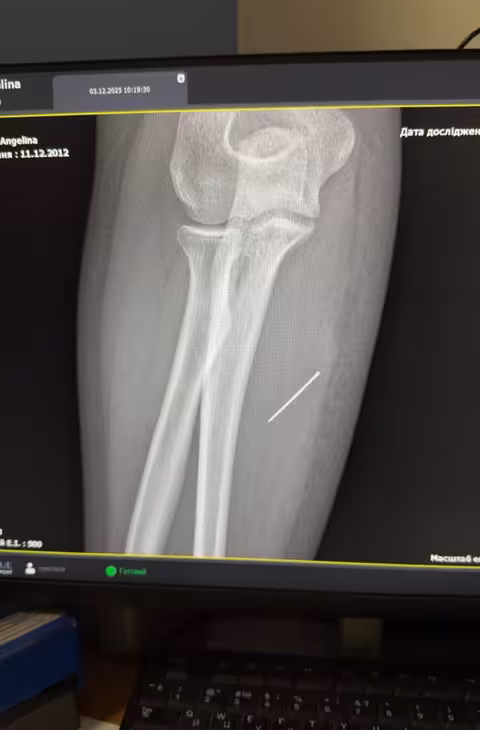

Під час обстеження хірурги запідозрили наявність стороннього предмета. УЗД та рентген підтвердили здогадки: голка зайшла під кутом 45 градусів і застрягла глибоко в м’язі. Більше того, металевий предмет продовжував мігрувати всередині тіла.

Лікарям було важливо витягнути голку точно за траєкторією її входження, аби вона не зламалася всередині. За допомогою спеціальної рентген-навігації хірурги виконали невеликий розріз і безпечно видалили сторонній предмет.